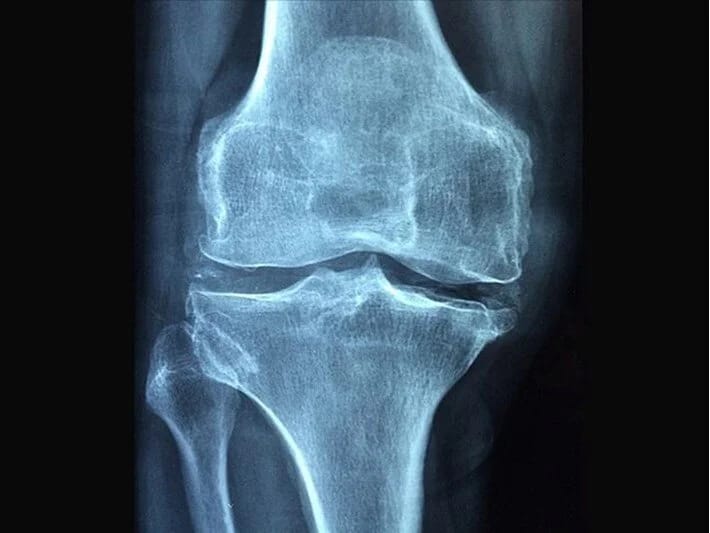

Sınıq sümüklərdə əməliyyatsız sağalma ümidi

7NEWS.az xəbər verir ki, Polşa alimləri tərəfindən hazırlanmış inqilabi dərman sınıq sümüklərə yeridilir və onları içəridən bərkidir, başqa vasitələrə ehtiyac olmadan sağalmağa imkan verir.